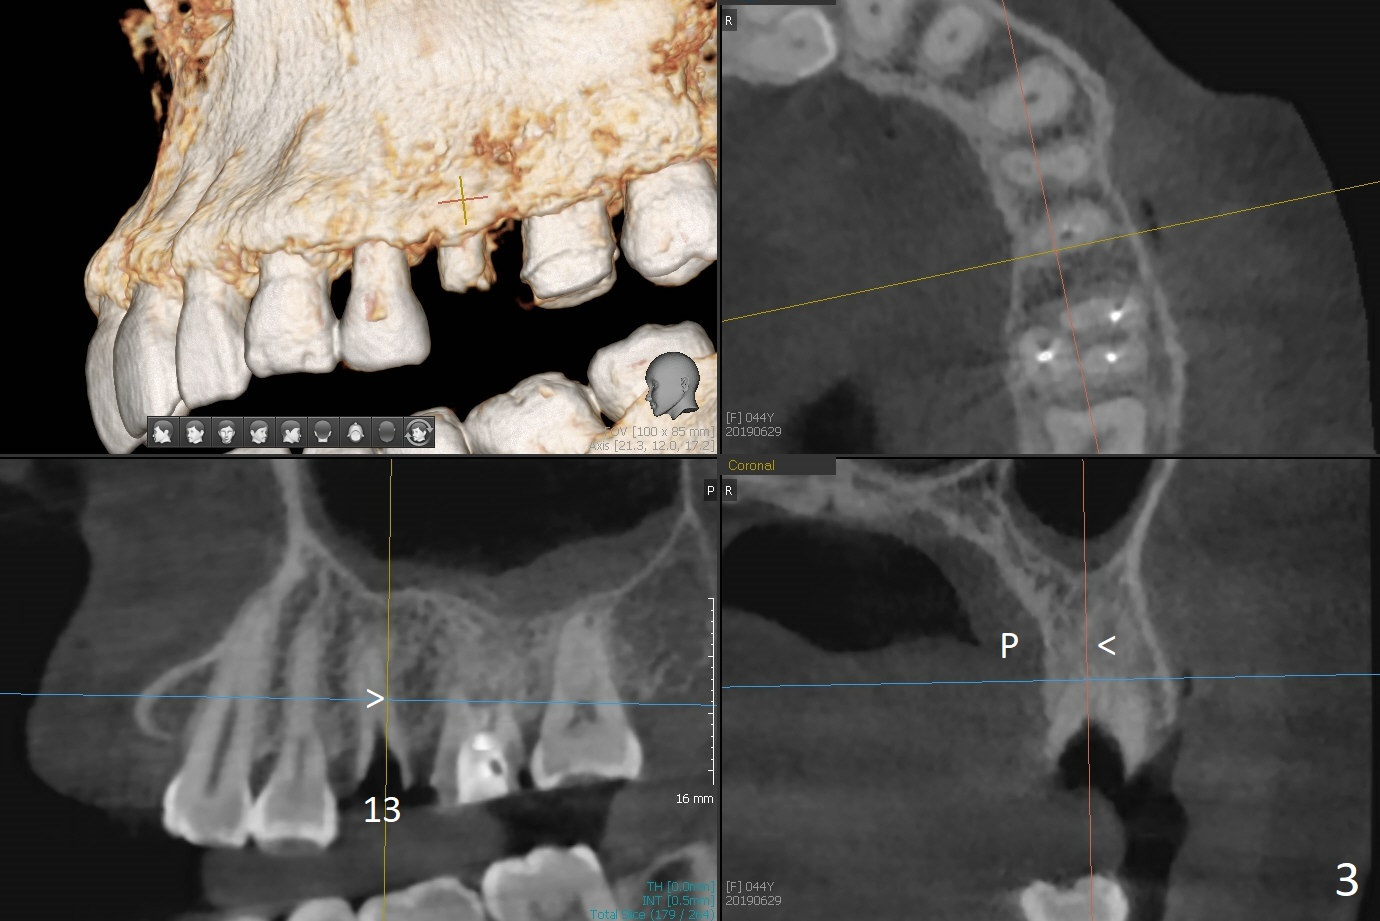

A 44-year-old woman used to have splinted crowns at #13 and 14 (Fig.1). Their dislodgement is due to residual roots at #13 and distal caries at #14 (Fig.2 ^). To avoid the distally curved apex of #12 and to have ideal trajectory of an IBS implant (Fig.4), osteotomy will be initiated in the distopalatal slope of the socket (Fig.3 arrowheads). The patient wants to correct the tooth #8 with rotation (Fig.5), which is due to a mesiodens (Fig.1,2 M). It will be accessed palatal (Fig.5 P). In fact there is percussion at #14 associated with MB2 (Fig.6 arrowheads) and PARL (*).